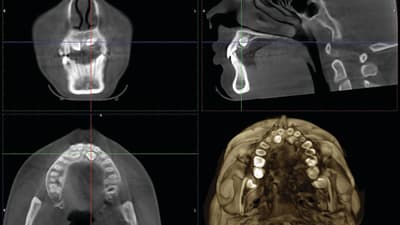

Article Take Only CBCTs on These Types of Orthodontic Cases Jack Fisher, DMD 10 reasons to use 3D imaging October 01, 2015 15 min read

Article Understanding ROI in CBCT Technology Brian Trava, DMD Multimodality and software capability should be at the top of your list October 01, 2015 5 min read